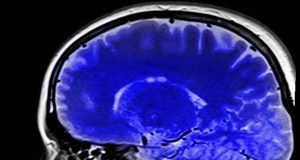

Dapatkah Sains Menjelaskan Tentang Kesadaran?

Hingga kini sains belum bisa menjelaskan bagaimana kesadaran (consciousness) bisa terbentuk di dalam otak kita. Otak manusia adalah organ manusia yang luar biasa kompleks,...